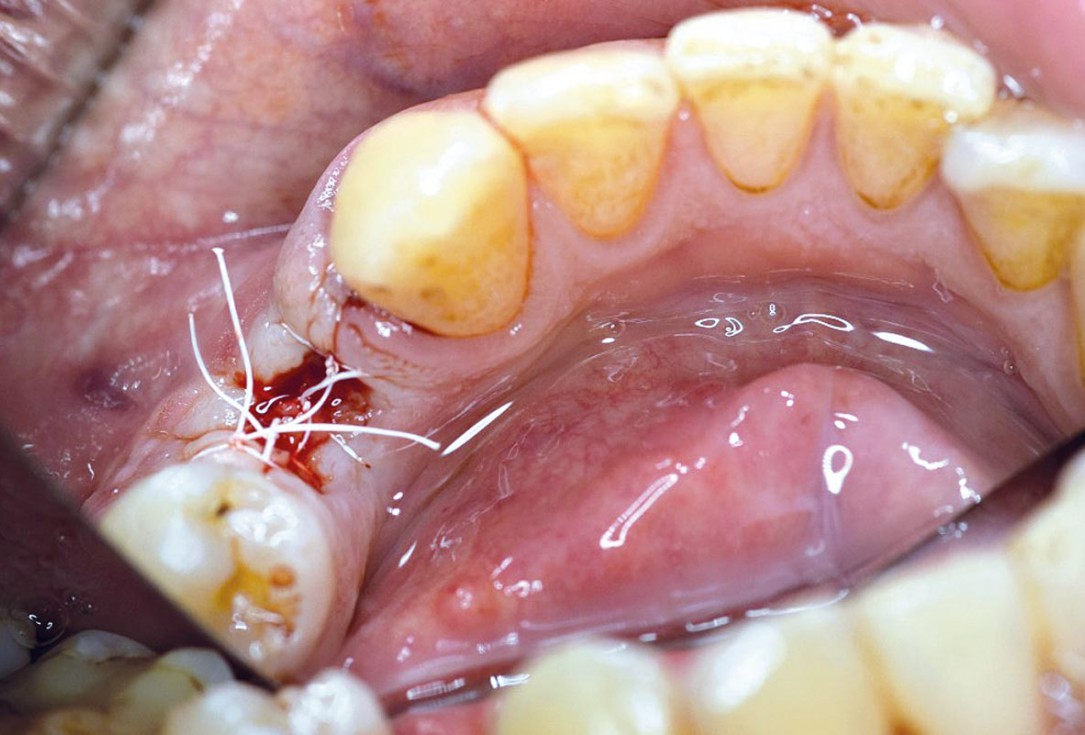

Posterior socket preservation using maxgraft® and permamem® - Dr. C. Landsberg

Initial clinical situation: 9 mm pocket depth associated with root fracture